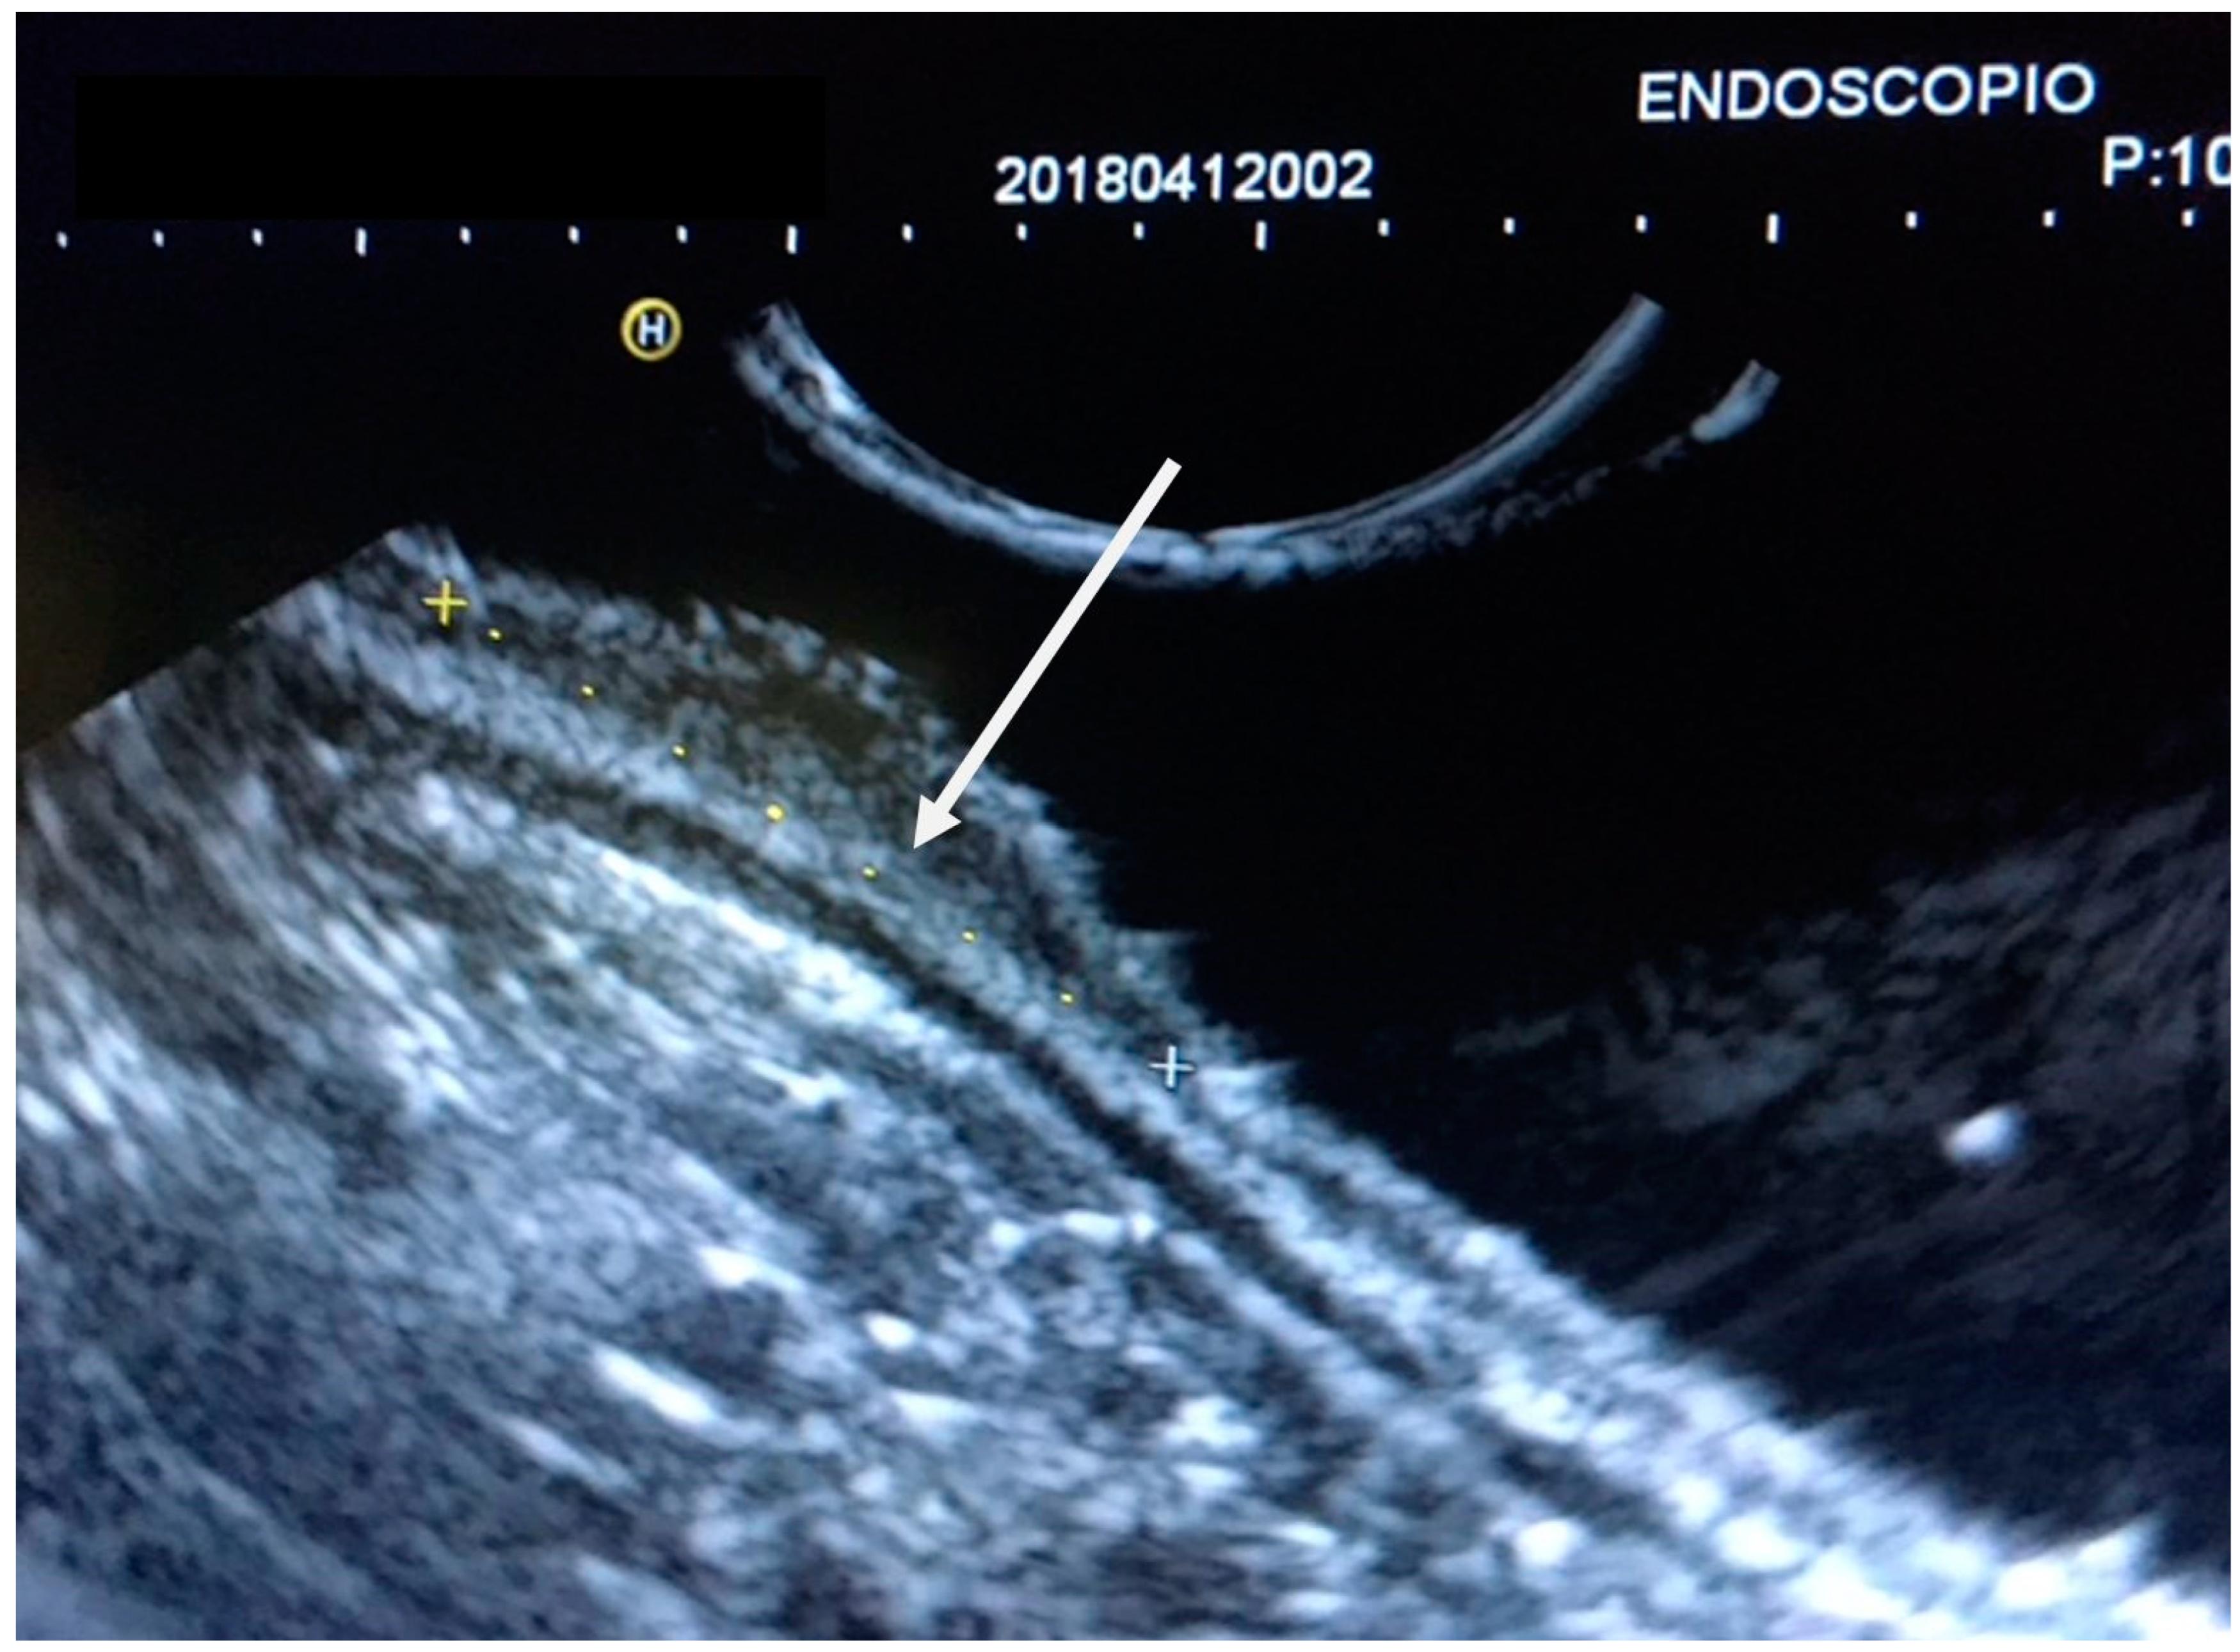

| EUS layer invasion | Mucosa | 155 (52.9) |

| Submucosa | 32 (10.9) | |

| Proper muscle | 32 (10.9) | |

| Subserosa | 74 (25.3) | |